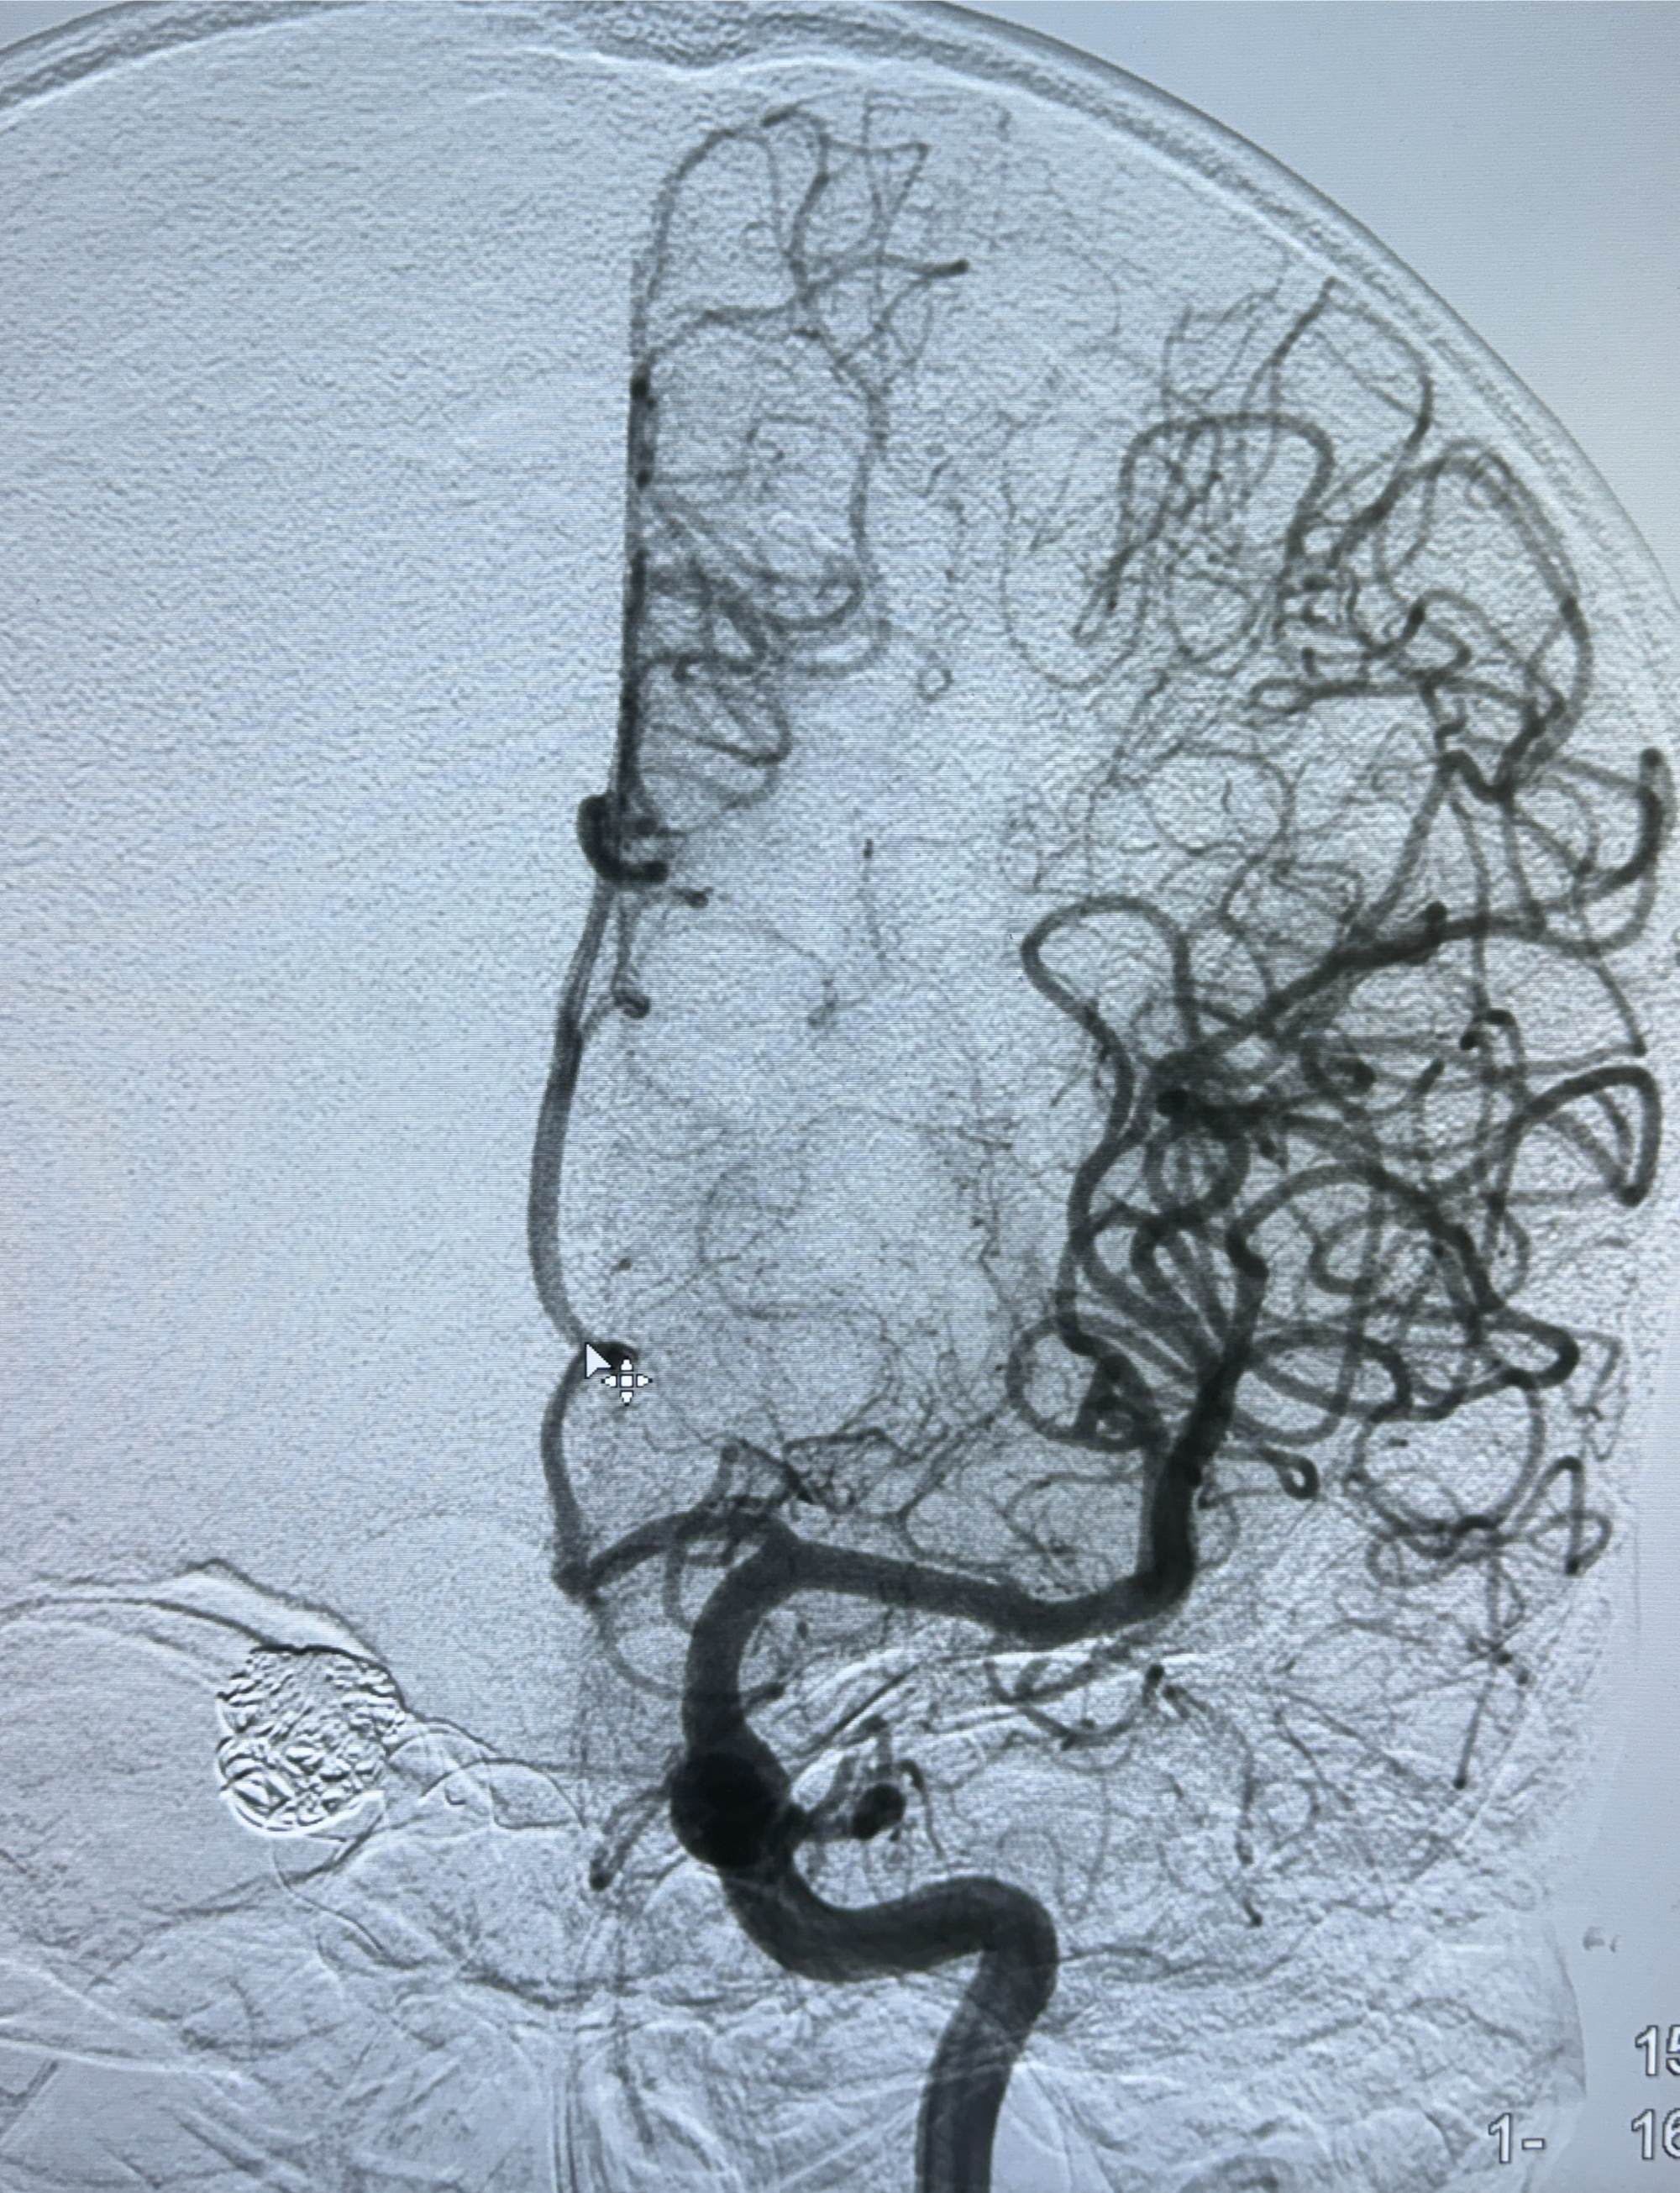

2024-01-08DSA:右侧椎动脉V4段夹层动脉瘤双支架辅助弹簧圈栓塞术后

患者支架辅助治疗后18个月,动脉瘤痊愈